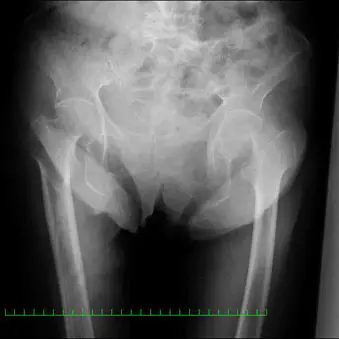

89歳女性。自宅にて歩行中に転倒受傷し、当院の救急外来へ搬送された。来院時の股関節単純エックス線像(図1)において左大腿骨頚部骨折(Garden3型、Müller AO分類31-B2)を認め、手術施行目的にて当科入院となった。受傷前のADLは杖を使用して独歩可能であった。既往歴は高血圧、高脂血症、アルツハイマー型認知症。また入院時諸検査において特記すべき事項はなかった。

(図1)単純レントゲン像